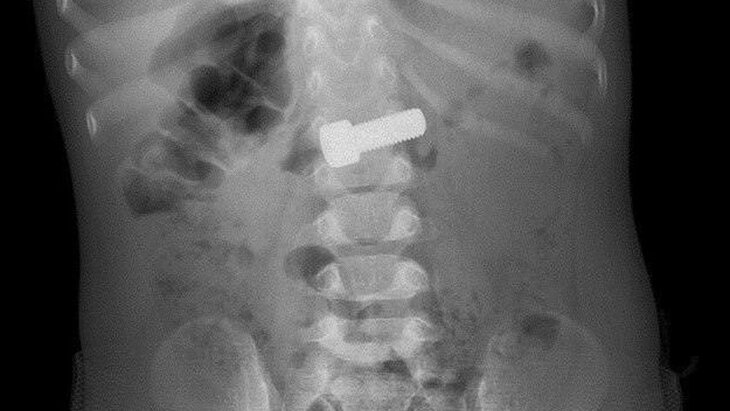

Фото: министерство здравоохранения Московской области

В ведомстве отметили, что годовалый мальчик случайно проглотил металлический болт. По итогам рентгенографии врачи подтвердили наличие крепежного изделия в желудке ребенка.

В ходе операции, продолжавшейся около 15–20 минут, медики успешно извлекли болт при помощи эндоскопической петли. Благодаря их слаженной работе мальчик избежал серьезных осложнений, таких как кишечная непроходимость и повреждение стенок желудка с риском развития перитонита.